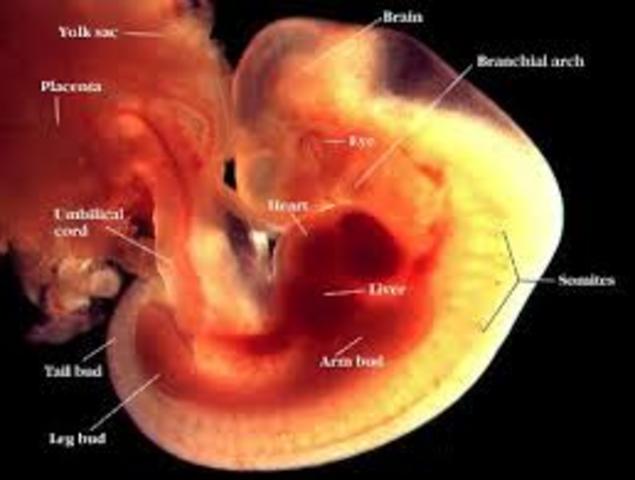

Period of the Embryo

All stages of the embryoTime period lasts from 2 weeks after conception until 2 months after conception.

MonthTwo of Pregnancy the baby continues to develop internal organs and other major structures of the body. the baby’s heart is developing. By the end of this week the baby’s heart will begin beating. For the next few weeks the baby will be at the Embryo stage of development. Pregnancy hormones have caused the mothers breasts to grow and mature, and she also experiences morning sickness

The nose, mouth, and ears are beginning to take shape. the mother may feeling moody one day and joyful the next.

The baby's fingers and toes are webbed now, his eyelids practically cover his eyes, breathing tubes extend from his throat to the lungs, and his tail is just about gone. the mother may notice that your bra is getting more snug.This is the time were the mother may start the morning sickness stage